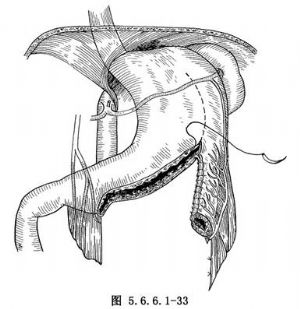

利用胃大弯制成长管用以重建食管。患者取仰卧位,腹部正中切口及左颈部切口或侧卧位左侧胸腹联合切口,游离大网膜,在幽门附近结扎切断胃网膜右血管,保留胃网膜左血管。在距幽门5cm处由垂直方向切开胃大弯约3cm,由此切口靠近大弯侧置入一根10cm长、直径为2cm的硬质胶管,沿此胶管切开胃前、后壁直至肝底,用细丝线间断缝合两层(图5.6.6.1-33)。如此制成的胃管可逆转向上提至颈部与食管作吻合(图5.6.6.1-34)。此术式的优点是能保留大部分胃在正常位置,缺点为缝合线过多,手术费时间,术后发生吻合口瘘及缝线边缘瘘的机会较多,近年已较少应用。